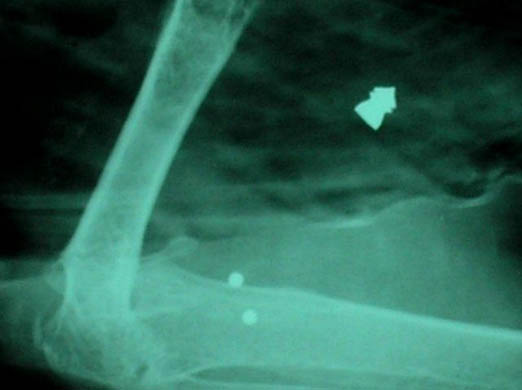

An x-ray of a swan, who has been severly injured

An x-ray of a severely injured swan which was shot by an airgun. The RSPCA has reported that more animals are becoming the victims of airgun attacks Photograph: RSPCA/PA